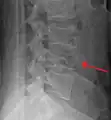

A burst fracture of L4 as seen on plane X ray

A burst fracture of L4 as seen one plane X ray